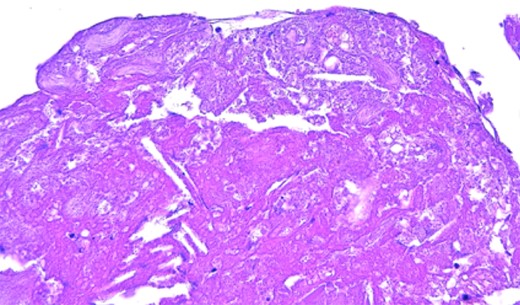

Patient resumed oral feeding on the first day after operation, and TEVAR using Zenith alpha (Cook, Bloomington, USA) for descending aortic aneurysm was performed on the 28th day. The patient was discharged by Day 59 post-surgery with no complication, and there was no recurrence of abdominal symptoms or findings suggestive of intestinal ischemia throughout the course. The white material collected intraoperatively was found to be cholesterol crystals as a result of the pathological test (Fig. 3).

Colonic ischemia after endovascular aortic repair (EVAR) occurs in 1-3% of patient, but intestinal ischemia after TEVAR seems to be a rare complication [6]. Zahn et al. reported the early and 1-year post-operative results of TEVAR for 191 patients with thoracic aortic disease. The results stated that among the reported patients, there were no reports of complications as SMA embolism or intestinal ischemia [7]. In our case, a thrombus in the aortic wall by the distal side of the stent graft was considered to be an embolus. Pathological findings also suggest that. TEVAR seemed to be the cause of this SMA embolism. Later, when TEVAR was performed on the descending thoracic aortic aneurysm, it was placed as to prevent any recurrence.